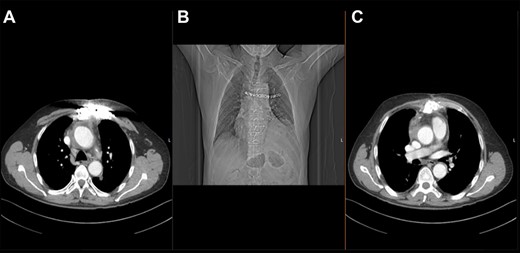

The histological analysis confirmed different stages of infection and inflammation of the resected aorta. Pseudomonas aeruginosa was cultivated from the intraoperative cultures. The patient received a combination of three antibiotics for 7 days, followed by single gentamicin treatment for another 10 days. The scar healed without any signs of inflammation. The control CT scan showed good consolidation of the sternum with no signs of infection (Fig. 3).

Post-operative thoracic CT scan; (A) chest wall reconstruction in transverse sectional plane; (B) topogram showing sternal wires and titanium plate arrangement; (C) chest wall closure and aortic homograft with small seroma collection in transverse sectional plane.